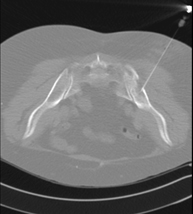

- CT-guided thoracic biopsy

It consists of obtaining a tissue sample from a specific thoracic lesion, such as the lung, mediastinum, sternum, etc. It is sometimes performed under sedation with the help of an anaesthesia team. Needles are used to draw a cylinder sample from the lesion to be studied, which is then sent to the Pathology Department for histological analysis. The entire procedure is monitored using images obtained by computed tomography (CT) at various stages of the biopsy, using CT fluoroscopy. After the test, the patient remains in hospital under observation. Coagulation tests must be performed before the puncture.

- CT-guided bone biopsy

Invasive examination used to extract bone tissue samples, mainly from tumours. The CT scan is used to select the puncture site and guide the biopsy needles to the tumour. Local anaesthesia is applied and sedation is occasionally used. The duration of the procedure will depend on its technical difficulty.